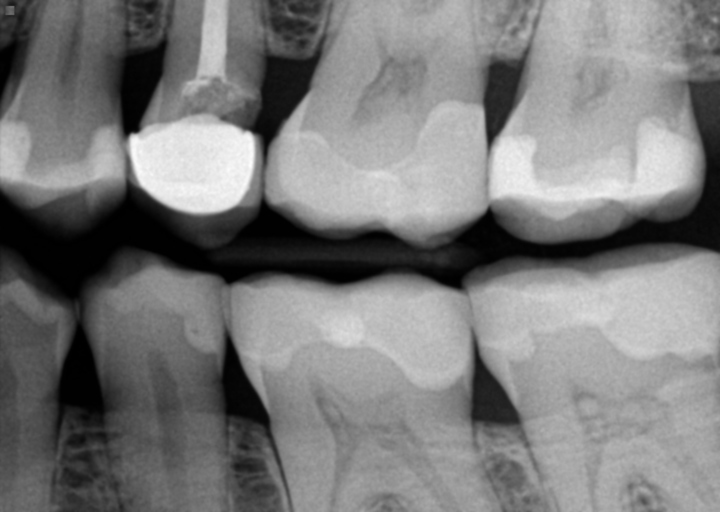

Root canal infection

I recently had a crown replaced and an infection developed after 6 months. Root canal work redone by entodontist and Denise agreed to redo crown at no cost. How long after a new crown woule i know if caused by leakage from improperly inttalled crown?When work was done the dentist worked ontwo teeth,the one with the recent rot canal work and another which had had root canal work. A post was billed for both teeth and temporary crown is in place. Shouldn't the 2nd tooth have had rot canal work? Having very sensitivity to hot and cold with the temporary. Will this diminishe with new crown in place?